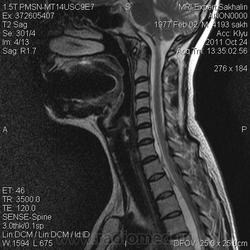

МРТ ШОП

Женщина с жалобами на боли в пояснице, но решила обследовать весь позвоночник.Травм, операций не было.Такие же изменения в грудном отделе.

1. Субархноидальная киста

2. Лизированная субдуральная гематома.

3. Менее вероятнее эпиема (но это только при условии соотвествующей клиники...)

Думаю все же №1... № 2 - это запасной вариант. Послушаем, что скажет общественность

Мультилокулярная экстрадуральная менингеальная киста